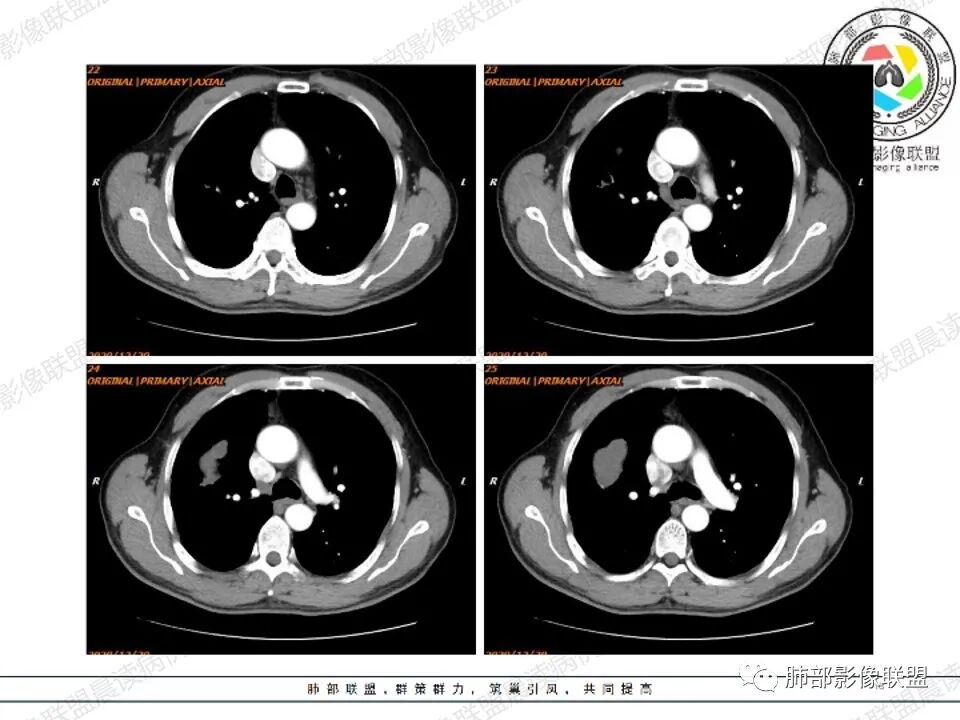

一切∮随缘:

左肺下叶肿块影平行支气管生长,边缘有纤维索条影,整体边缘平直,略彭隆,边界清楚,伴行支气管堵塞,周围伴有肺气肿,增强扫描强化不明显,无明显实性病变,考虑良性,支气管闭塞?支气管囊肿?平滑肌瘤。

小强:

左肺下叶孤立性肿块,形态规则,密度均匀,边界清,周围可以气肿及条索,无强化,左肺下叶后基底段支气管未见发育?考虑发育畸形,支气管囊肿 ?闭锁?先天性囊性腺瘤样畸形?

采莲:

老年女性,查体发现,左肺下叶不规则实性肿块,边缘平直收缩,无毛刺,周围有纤维牵拉及肺气肿,强化不明显。先天肺发育不良,支气管闭锁。

穿越七海的风:

左肺下叶扁平形结节,边缘光滑平直,边界清晰,周围肺气肿,强化不明显,支持先天肺发育不良,支气管囊肿

巴伟:

左肺下叶不规则高密度早灶,边缘平直为主,界清,周围有肺气肿,无强化,考虑良性病变,支持先天肺发育异常,支气管闭锁,鉴别支气管囊肿,囊腺瘤样畸形。

蔣勝華:

左肺下叶高密度,边缘光滑,周围肺气肿,强化不明显,ccam?鉴别 隔离

优彤:

左肺下叶肿块,边缘光滑,支气管动脉伴行,周围肺气肿,考虑支气管闭锁